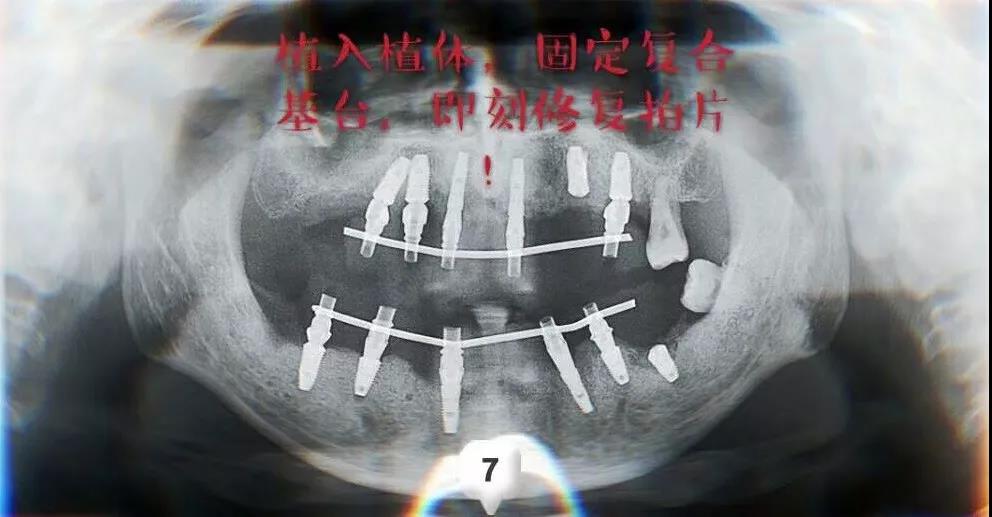

ЁЁЁЁОЙ§вЛжмЕФЛжИДЪБМфЃЌНјааСЫЯТАыПкЕФжжжВЃЌВмжїШЮСЊКЯжжжВЬхМгЙЄГЇЕФММЪІИЯЙЄжЦзїЭъГЩСЫШЋПкЮобРђЂЕФМДПЬаоИДЃЌРњЪБ12ИіаЁЪБЃЌЪжЪѕНсЪјЪБвбОЪЧЭэЩЯ10ЕуЖрЃЌЛМепгжПЊГЕИЯЛиСЫББОЉЁЃ

ЁЁЁЁМДПЬжжжВМДПЬаоИДЗНАИЃЌБЃеЯМжЯШЩњФме§ГЃНјЪГШэЪГЃЌЛжИДбРГнЦыећЪБЕФдЪМУцУВЃЌД§АВзАЩЯгРОУадЕФжжжВбРЙкБуПЩЛжИДе§ГЃОзНРЙІФмЁЂе§ГЃИКжиСЫЁЃ